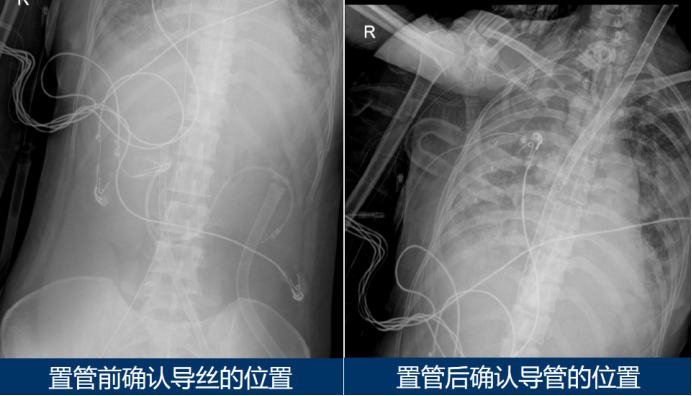

1)管路评估:通过床旁超声确认静脉插管位置,判断是否存在再循环,双腔管需通过影像学检查验证位置准确性(图2)

2  双腔管位置的确认